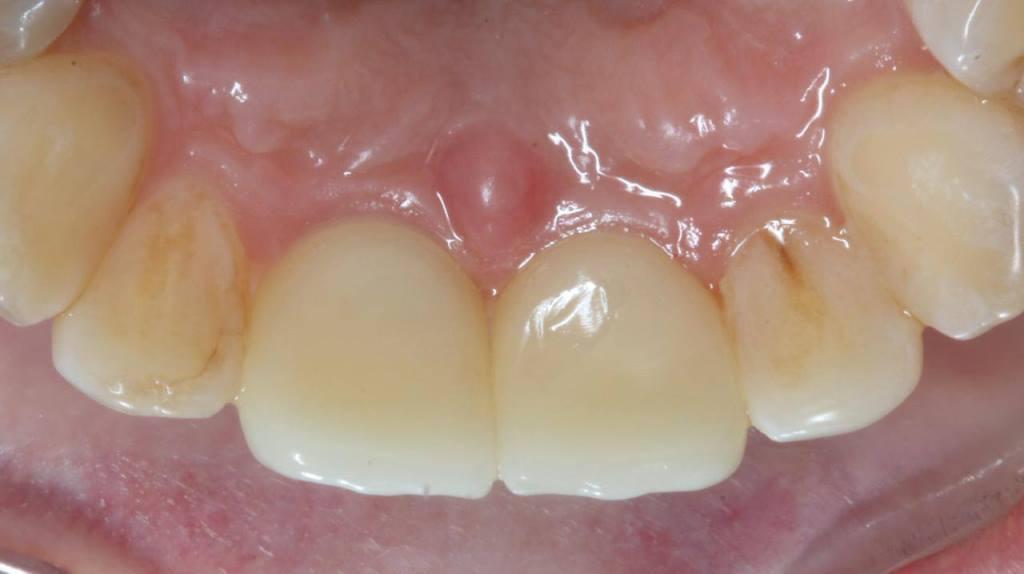

Фото 2.

Но! Воссоздать, восстановить то, что дано природой всегда сложнее, чем сохранить! А сохранить есть что: объем костной ткани, уровень мягких тканей - симметрию зенитов и межзубные сосочки! Во фронтальном отделе это критически, экстремально важно. Особенно при высокой линии улыбки, когда обнажаются не только зубы, но и десна.